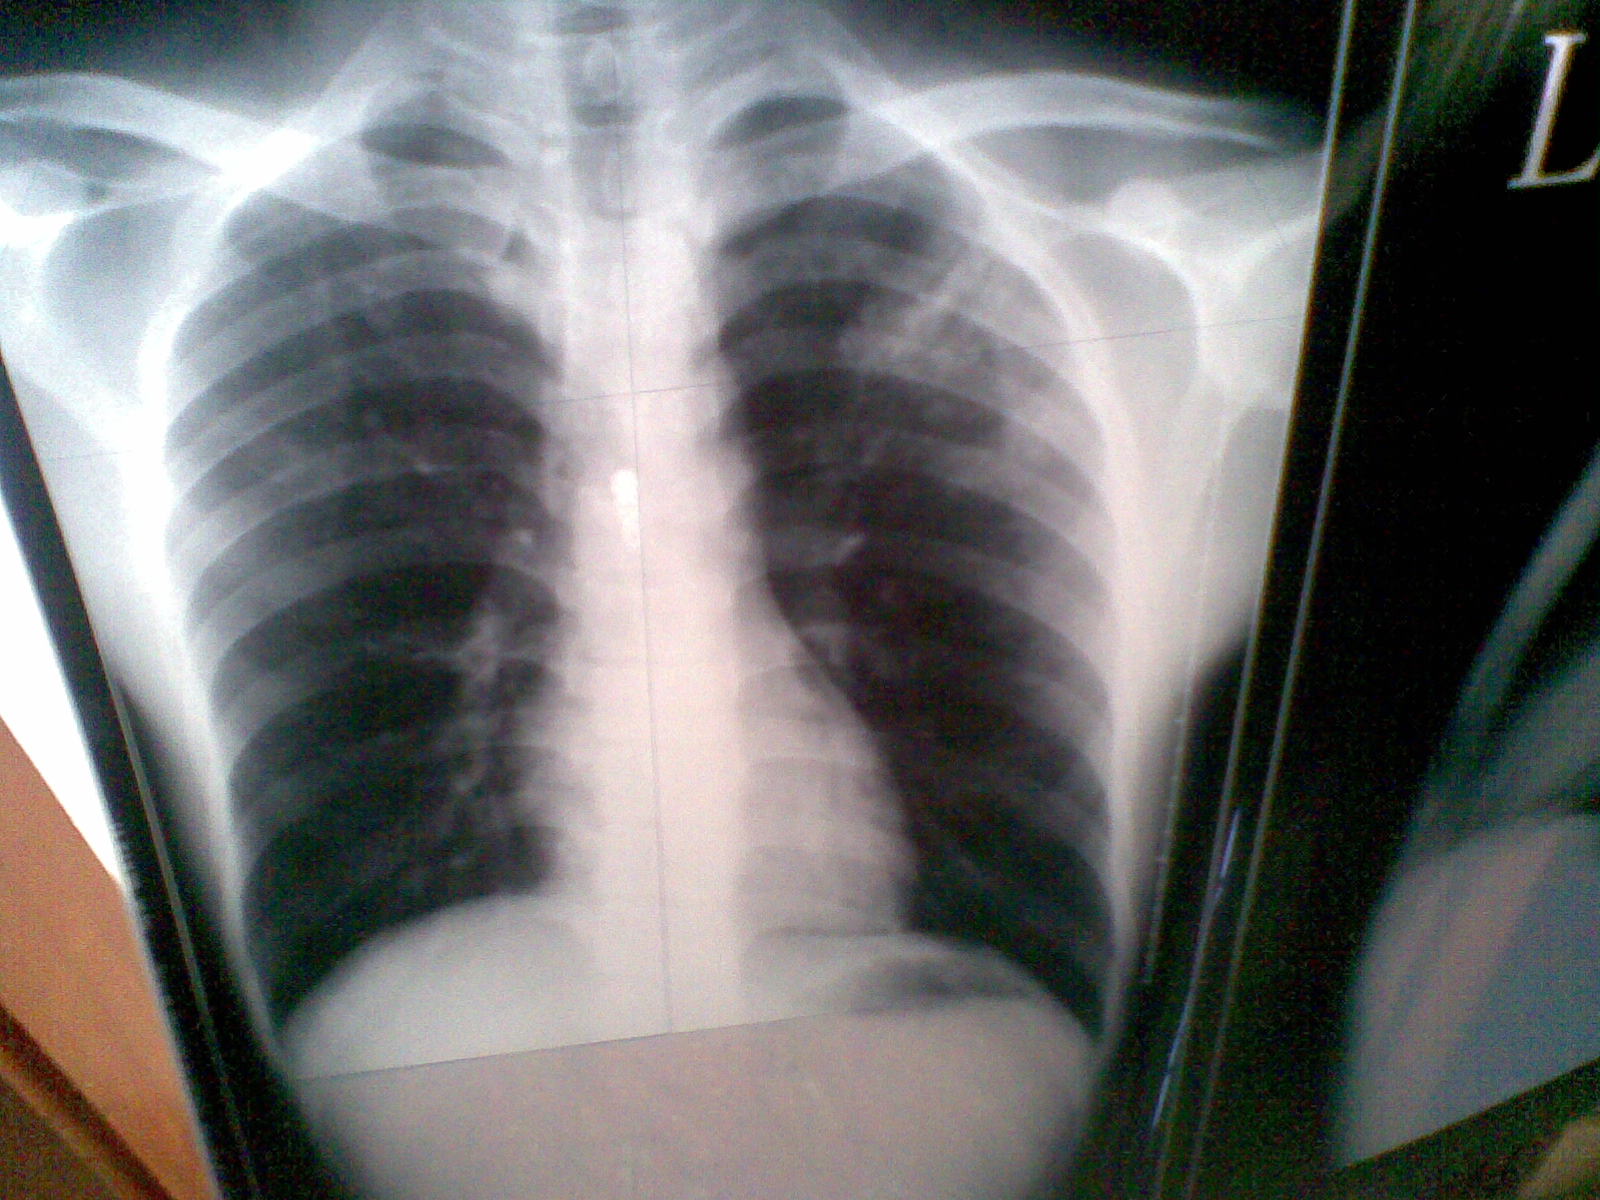

浸润型肺结核(图)

浸润型肺结核

浸润性肺结核表现最多样,最突出的表现就是会产生典型的结核结节及

大叶性炎.胸部 x 光胶片显示泡浸润在右中叶结核感染

肺结核 (tb): 胸部 x 光显示肺泡浸润在这两个由于结核杆菌感染的肺